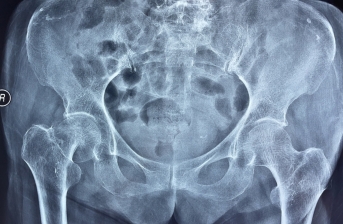

术前x线片 术后x线片

两周前,92岁的文大爷和94岁的杨奶奶均因不慎摔倒,右侧髋关节疼痛难忍,前往广元市第一人民医院骨科就诊,经ct检查,确诊为右股骨颈骨折,收治入院。